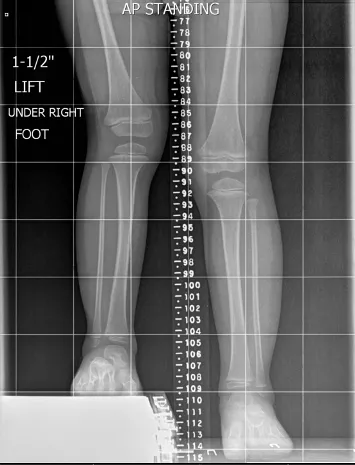

1. Pre-Operative Planning – X-rays, CT scans, and software planning to calculate correction.